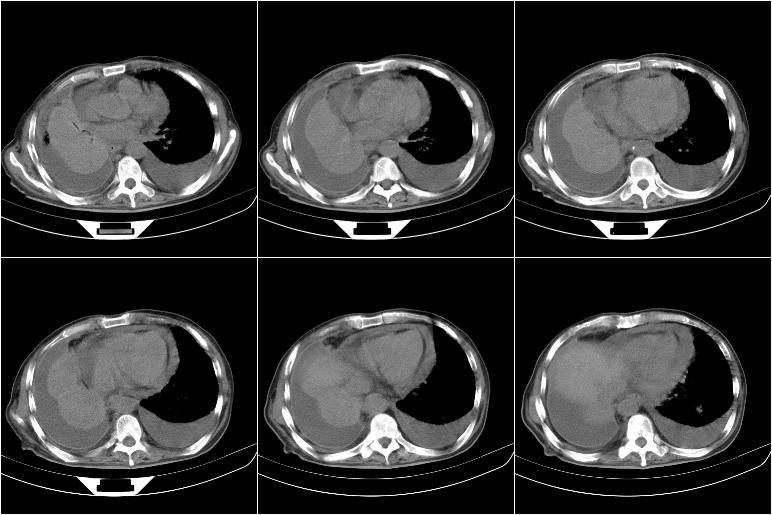

以下是引用边生丽在2009-8-17 11:43:00的发言:[br][br] [br] 右肺中心型癌伴右肺下叶不张、双肺转移并癌性淋巴管炎、心包和双侧胸腔积淮(转移?)、脑转移、肝转移、多骨(颅骨、椎骨)转移。 [br] [br]

以下是引用随光逐影在2009-8-17 14:09:00的发言:[br]支持 右肺中央型癌伴右肺下叶肺不张,纵隔淋巴结转移,双肺转移并癌性淋巴管炎,心包和双侧胸腔积液,脑转移、肝转移、多发性骨(颅骨、脊椎)转移。